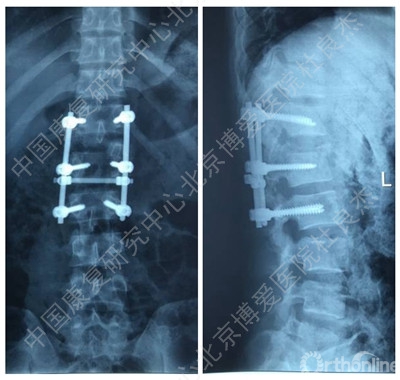

伤后当天在全麻下行“后路探查减压复位椎弓根钉内固定植骨融合术”。手术后给予综合治疗,患者双下肢肌力较术前好转,但仍存在无力及感觉异常,大小便功能无明显改善。为进一步康复治疗及训练就诊中国康复研究中心北京博爱医院,以“腰椎骨折术后并脊髓损伤”收住院。患者近期精神、饮食、睡眠好,小便留置尿管,大便需借助开塞露。

X线片

手术后辅助检查

辅助检查

3、胸12椎弓根钉断裂